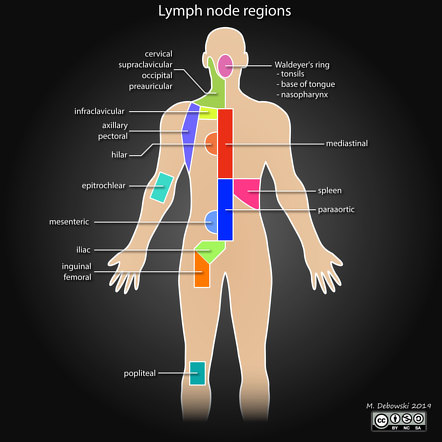

lymph nodes regional lymphoma seer node regions anatomy diaphragm preauricular man above staging cancer hodgkin anatomical

Ann arbor staging system. Lymph system lymphatic nodes abdomen presentation ppt node mesenteric superior intestinal powerpoint inferior trunk. Hilar lymph nodes map